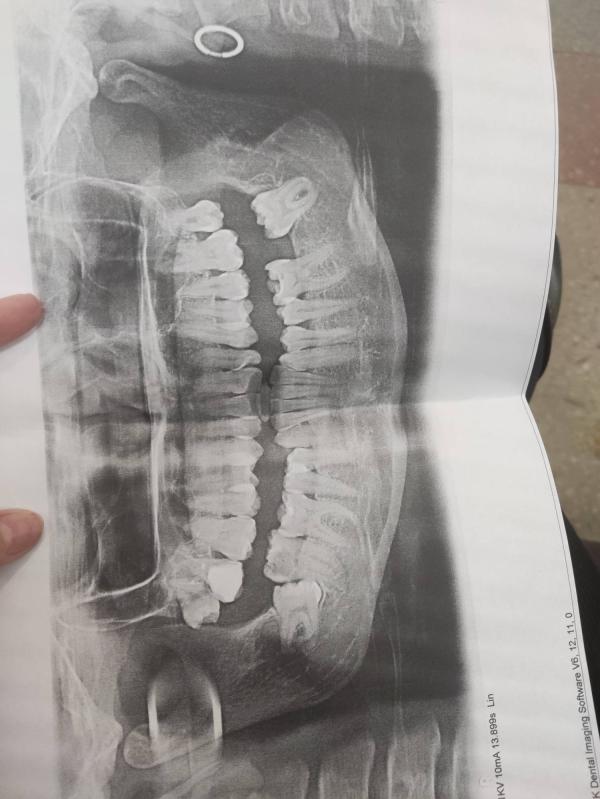

Нужно вырвать зуб который стоит боком на нижней челюсти

На ренгене сказали надо резать